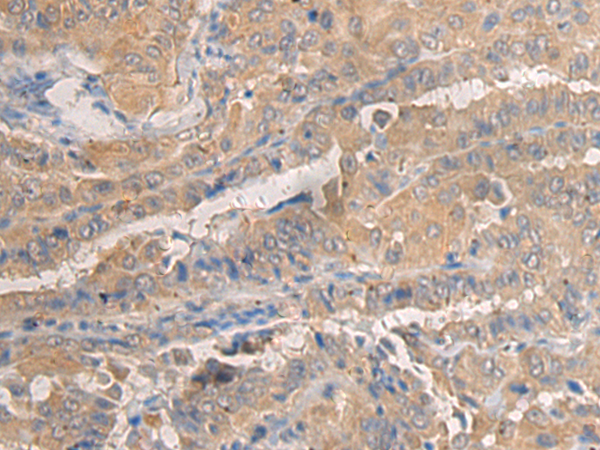

IHC positive control: |

Human thyroid cancer and Human breast cancer |